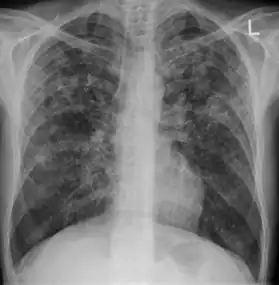

In active pulmonary TB, infiltrates or consolidations and/or cavities are often seen in the upper lungs with or without mediastinal or hilar lymphadenopathy.[1] However, lesions may appear anywhere in the lungs. In HIV and other immunosuppressed persons, any abnormality may indicate TB or the chest X-ray may even appear entirely normal.[1]

Old healed tuberculosis usually presents as pulmonary nodules in the hilar area or upper lobes, with or without fibrotic scars and volume loss.[1] Bronchiectasis and pleural scarring may be present.